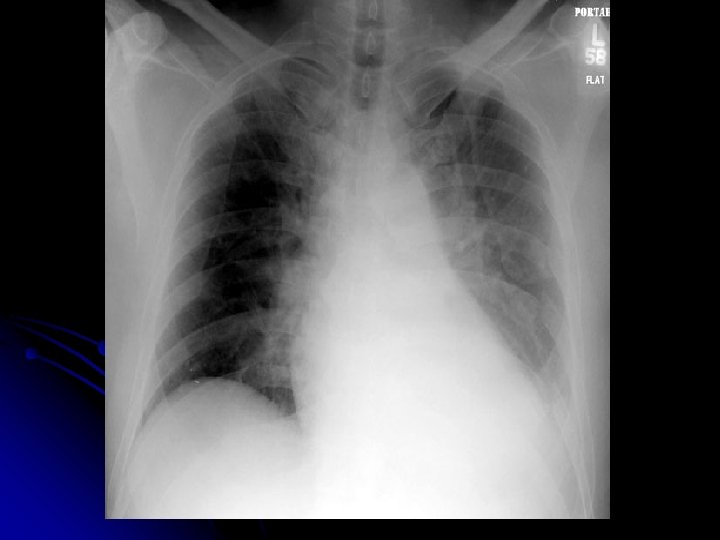

l ŞİKAYETİ Kuru öksürük Şiddetli sağ yan ağrısı Dispne Aniden şikayetleri başlamış.

l Olası Tanılar? l Plöretik ağrı; Plörezi, l AC infarktı/ AC CA l Pulmoner Emboli l İnf. l Pnömotoraks

FİZİK MUAYENE Siyanoze Dispneik DSS: 32 Sağda hipersonorite OSKÜLTASYONDA Sağda solunum sesi alınmıyor.

l Olası Tanılar? l Pnömotoraks? ? ? l Kitle? ? ?

l Tanı Tedavi